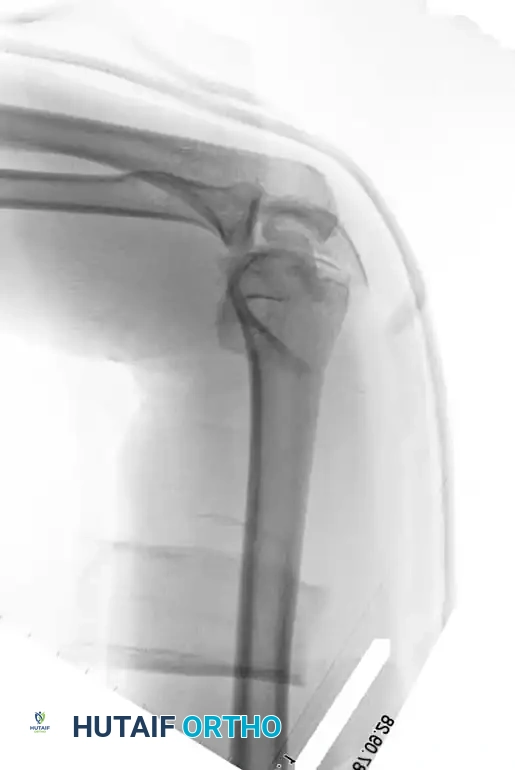

Plating Configurations: Orthogonal vs. Parallel

Historically, the standard technique involved placing plates at orthogonal angles (90-90 plating), typically with a medial plate applied to the medial ridge and a lateral plate applied to the posterior surface of the lateral column.

Image

Fig. 3: Supracondylar fracture with intra-articular extension fixed with 90-90 locked plates through an olecranon osteotomy approach, and subsequent hardware removal.

However, modern biomechanical studies (e.g., Self et al., Schemitsch et al.) have demonstrated that parallel plating (direct medial and direct lateral plating) provides superior resistance to torsional forces and axial loading, particularly in the presence of severe metaphyseal comminution. Precontoured anatomical locking plates have largely replaced one-third tubular and 3.5-mm reconstruction plates, which are prone to fatigue failure in complex patterns.